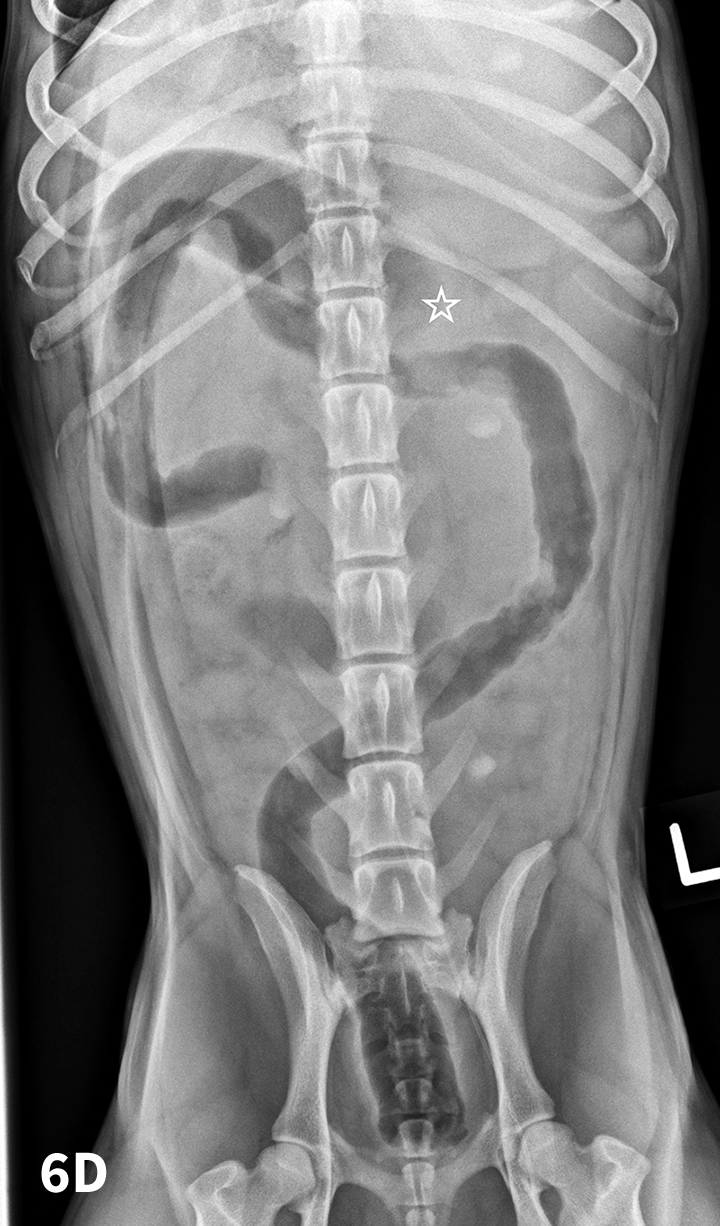

Learning Radiology Lead, poisoning, plumbism, intoxication, ingestion Lead Foreign Body Lead poisoning is a serious health problem that affects multiple body systems and is particularly harmful to young children and. Foreign body (fb) and food impaction are one of the most common gastrointestinal complaints seen in the. Foreign bodies may be introduced into the skin through lacerations and soft tissue wounds. Lead Foreign Body.